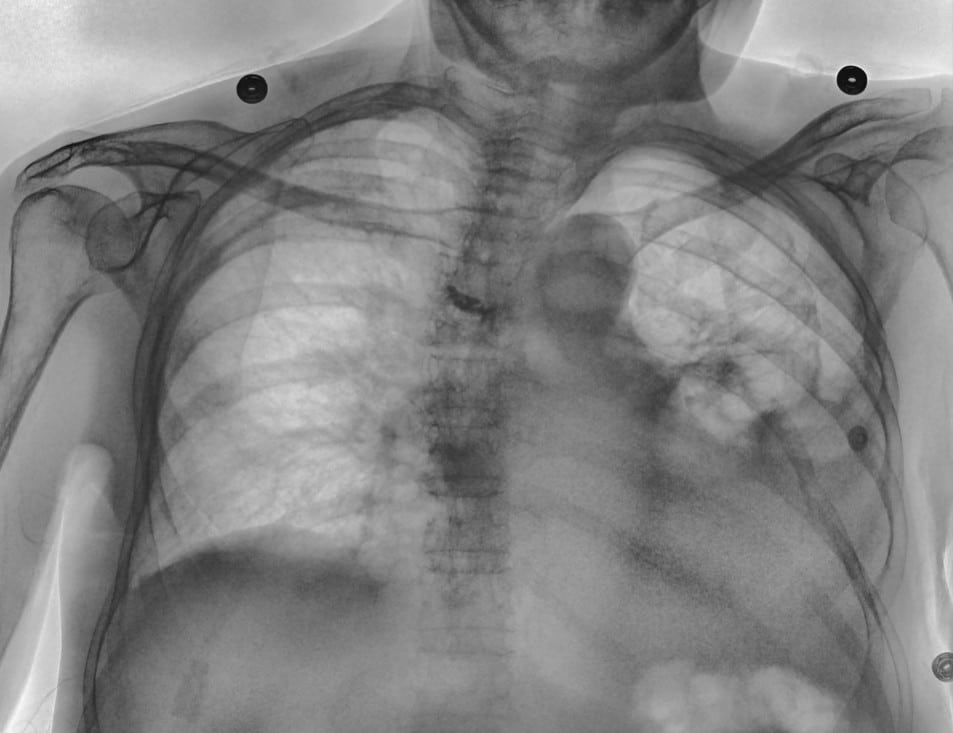

In this case, the conventional DR image shows subtle findings. The spectral soft-tissue image reduces overlying bone, making the pneumothorax more conspicuous. The corresponding bone-selective image highlights a rib fracture, a potential underlying cause of the pneumothorax.

Pneumothorax Evaluation

Soft-tissue images reduce rib overlap and may improve visualization of pneumothorax in trauma patients.

Rib and Skeletal Trauma